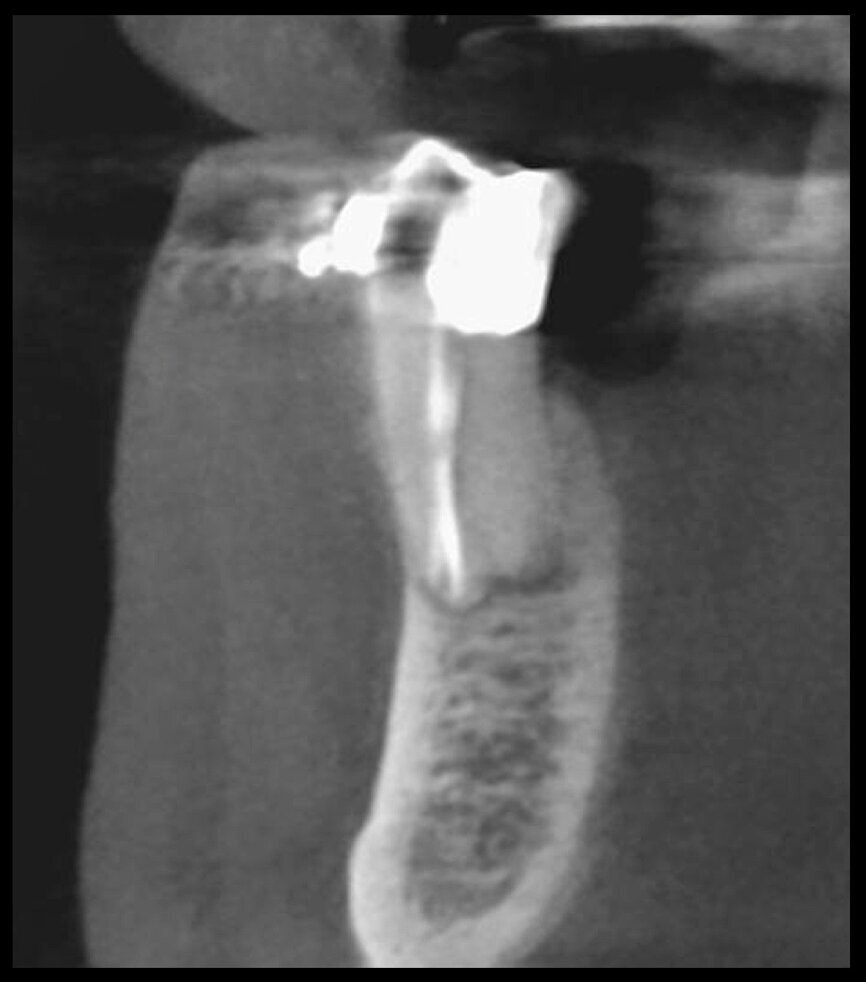

Undeniably, one of the most complex conditions to treat is external invasive root resorption, where the extent of the defect affects the treatment options. It therefore becomes sensible to perform a preoperative evaluation of the location and extent of the resorption, and the potential for recovery, thus, depends on correct 3D planning of the procedure, which can only be achieved after examination of the CBCT images. It is very important to be able to view the slices of the tooth correctly in all three planes, focusing in particular on the axial slices, which will prove to be strategic from an endodontic diagnosis point of view.

Comparing the two teeth shown in Figures 10 to 22 demonstrates just how important it is to analyse all the slices of the CBCT study correctly. We can see that, in the maxillary molar, the lesion penetrates into the pulp chamber, starting from the root’s distal surface, but remains within the coronal third of the tooth, without significantly affecting the integrity of the pulp chamber floor (Figs. 10–15). The clinical images illustrate the operative treatment phases, from resorption debridement through to repair using bioceramic cement (Figs. 16–19). The final radiographic images confirm the validity of the conservative and endodontic treatment of the tooth. The situation is completely different for the mandibular molar, where the evaluation of the CBCT scan clearly reveals the extent of the resorption, which invades the pulp chamber floor until the furcation, a situation that cannot be determined from observing the preoperative radiograph alone (Figs. 20–22).